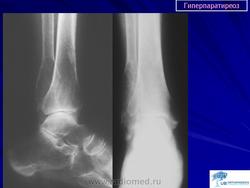

Пораженные длинные трубчатые кости несколько вздуты. Это цилиндрическое утолщение захватывает весь диафиз, метафизы также представляются несколько вздутыми. Кортикальный слой неравномерно истончается, может быть бугристым. Эпифизы, как правило, мало изменены. Характерна деформация метадиафиза бедренной кости по типу «пастушьей палки». Область большого вертела поднимается, анатомическая шейка бедренной кости располагается горизонтально, диафиз О-образно искривляется. Характерна также варусная деформация проксимального отдела плечевой кости. Деформации обычно не симметричны. Достаточно быстро развивается деформация костей таза в виде «карточного сердца». Реакция надкостницы отсутствует и лишь при патологических переломах, может выявляться незначительная периостальная реакция.

На рентгенограммах определяется перестройка костной структуры в виде очагового или диффузного крупнозернистого остеопороза. Характерна кистозная перестройка костной структуры. Кисты располагаются, как в зоне костномозгового канала, так и интракортикально. Форма их - овальная, вытянутая по длиннику кости. Кисты могут быть одиночными и множественными. Часто кисты сливаются одна с другой и в зоне костномозгового канала они имеют нечеткие контуры.